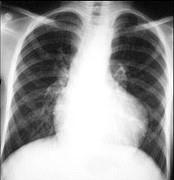

法洛四联症胸部X线检查最具特征性的表现是 ( )A.梨形心B.靴形心C.烧瓶心D.肺门阴影增大E.肺血管纹理增多

问题 法洛四联症胸部X线检查最具特征性的表现是 ( )

选项 A.梨形心 B.靴形心 C.烧瓶心 D.肺门阴影增大 E.肺血管纹理增多

答案 B